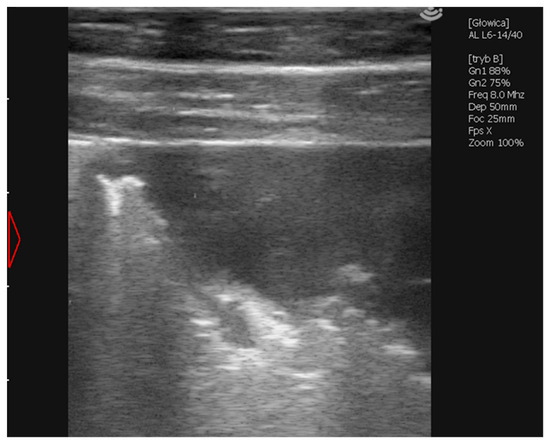

2.1.5. Case 3—Suspicion of Extrapulmonary Disorders